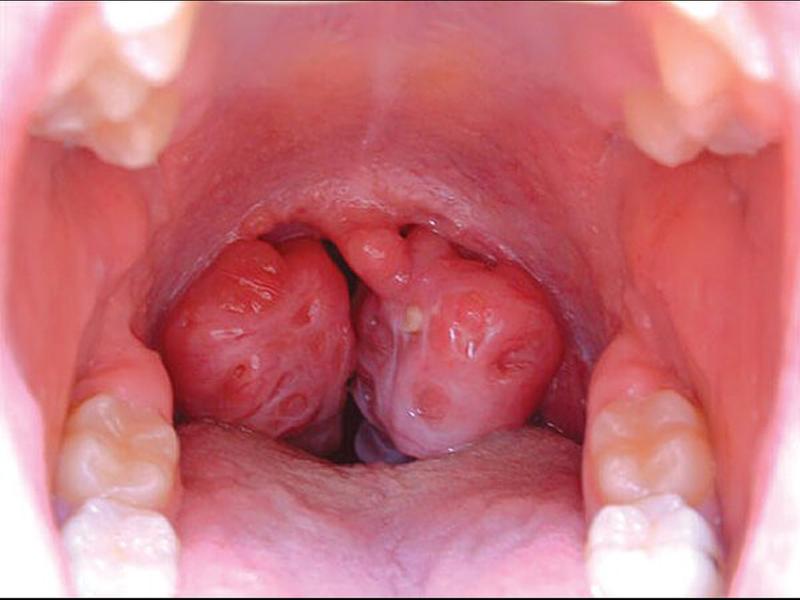

Ung thư vòm họng là loại ung thư tế bào vảy lót bên trong vòm họng, thuộc nhóm các ung thư vùng đầu cổ bao gồm: ung thư phần giữa của họng (ung thư hầu họng), ung thư phần trên của họng (ung thư mũi hầu) và ung thư phần dưới cùng của họng (ung thư hạ hầu).

Căn bệnh ung thư vòm họng biểu hiện qua các triệu chứng khác nhau tùy thuộc vào từng vị trí của các tế bào ung thư xuất hiện bên trong khu vực vòm họng. Bệnh nhân có thể nhận biết căn bệnh này thông qua các triệu chứng như: